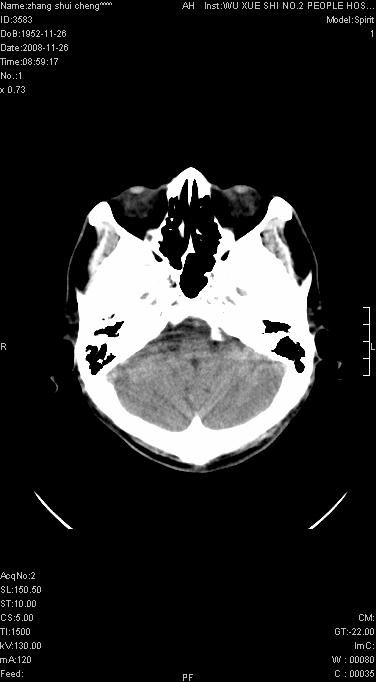

男.68.肢体无力多年

请问是蛛网膜囊肿.还是软化灶.原有中风

脑外性,蛛网膜囊肿

支持右侧颞区蛛网膜囊肿。

蛛网膜囊肿,软化灶周围脑沟应该受牵拉,扩大